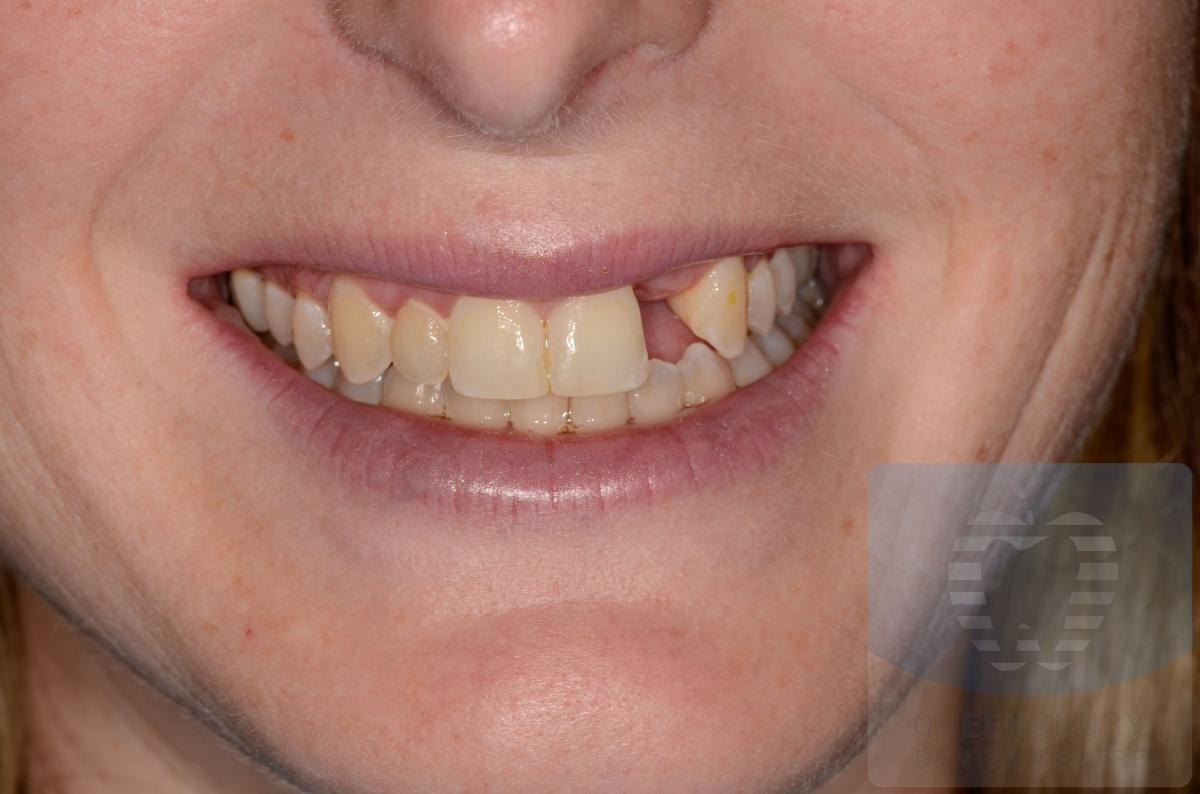

Missing teeth and loose dentures make many people avoid social settings because they are too self-conscious about their appearance. Current dental procedures, however, replace everything from a single missing tooth to a completely missing arch. Ask your dentist or dental specialist about the different dental options that are available to you. Don’t let another day go by without taking this important first step to restoring your confidence and your smile!